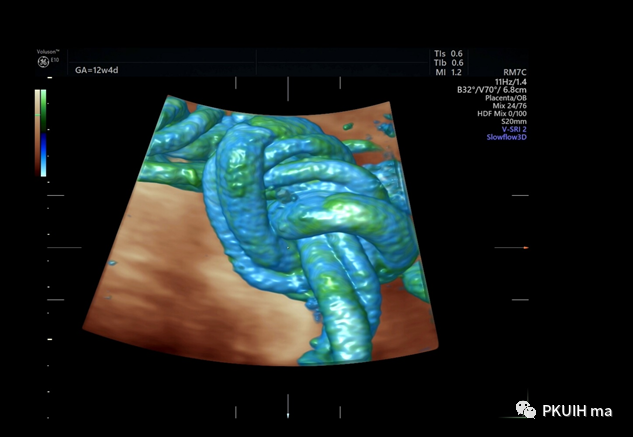

四维血流现象呈现脐带打结

脐带立体图像

四维血流显示脐带插入点和胎盘绒毛血管